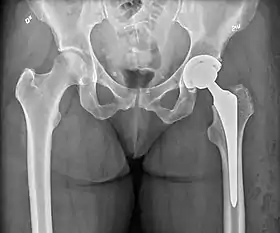

An X-ray showing a left hip (right of image) that has been replaced, with the ball of this ball-and-socket joint replaced by a metal head that is set in the femur and the socket replaced by a cup